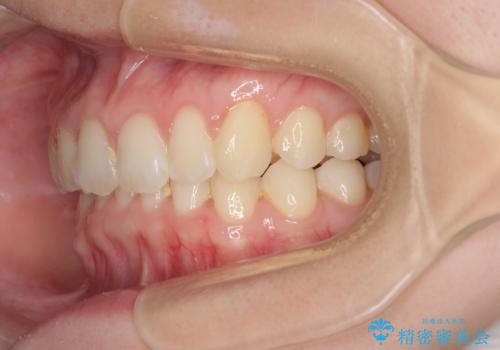

- 口元の深い咬み合わせ(ディープバイト)を気にして来院された患者様です。

インビザラインによる上下歯列の遠心移動(後方移動)により、口元のデコボコとディープバイトを改善することとしました。

下顎左右の犬歯とその後ろにある第一小臼歯、計4歯がシミュレーション通りに動かずディープバイトがなかなか改善されませんでした。

マウスピースの再製作を何度か行いましたがうまくいかないため、部分的にワイヤー矯正を併用することを提案しました。しかし、最も気になっていた前歯のデコボコはきれいに改善されたため、これ以上治療を希望されず、治療を終了することとしました。(今後気になった際には再開する予定です)